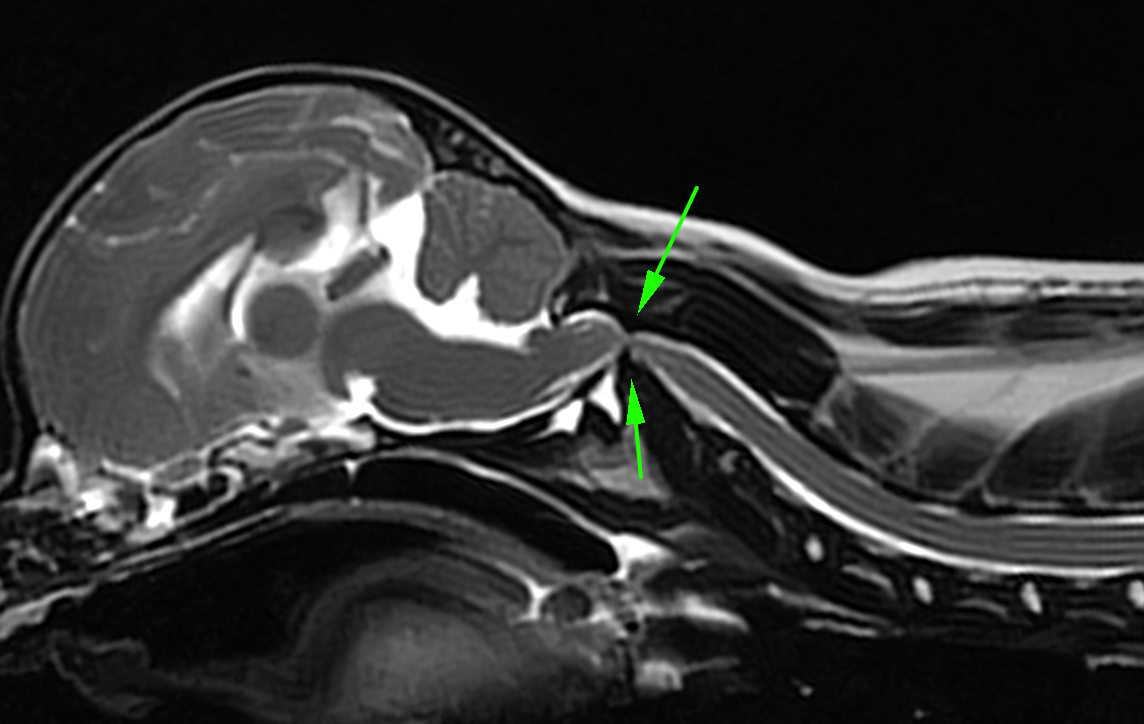

左がCT画像、右がMR画像です。2番めの頚椎である軸椎の歯突起が神経を圧迫してしまっているのがわかります。

別の症例。どこか痛がるという主訴で来院されました。確かに触るとどこかを痛がっている状態で、MRIを撮影すると脊髄空洞症が重度に認められました。その原因の一つとして環軸椎不安定症が関連しており、手術を行いました。

MRIでは重度に脊髄が圧迫されており、環軸椎の部分で脊髄が重度に狭窄しているのが分かります。